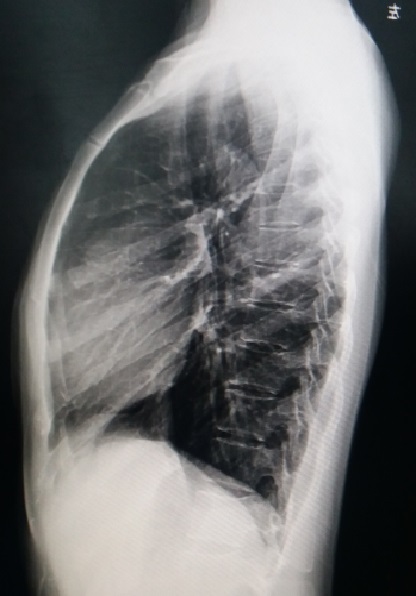

入院查体,患者前胸壁正中明显前突,两侧向后方倾斜,以前上胸壁明显,伴肋弓前突(图1)。未闻及心脏杂音,无脊柱侧弯,无其他畸形。X线检查提示前胸壁上半大面积前突(图2),心电图检查未发现异常。

图2 ,术前X 线检查。前胸壁前突明显。